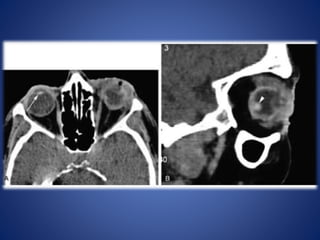

SUBPERIOSTEAL ABSCESS

Accumulation of pus between orbital wall (usually medial) and orbital periosteum.

SUBPERIOSTEAL ABSCESS Accumulation ofpus between orbital wall (usually medial) and orbital periosteum.

• #40 CT (C+ arterial phase) Increased attenuation of fat planes of left peri-orbital area with extraconal extension along the medial rectus muscle.